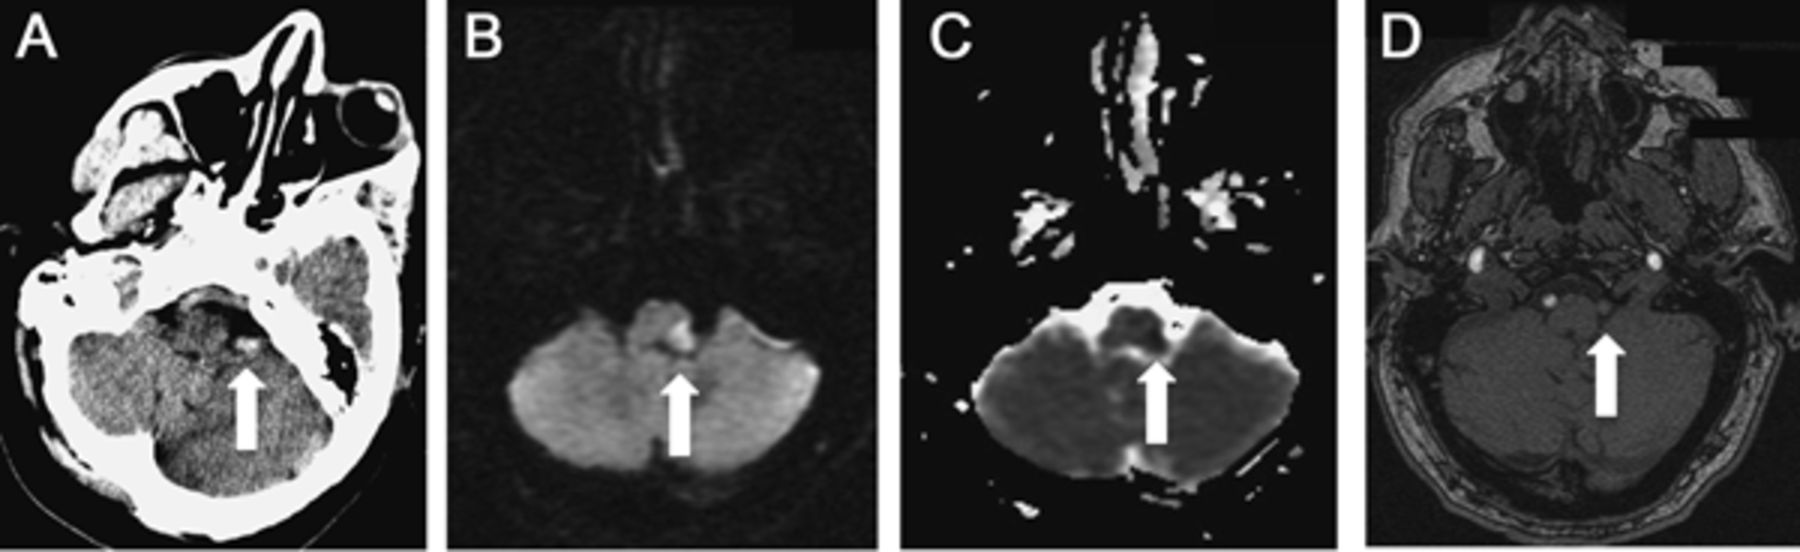

60岁的人与历史的高血压和血脂异常出现突发性眩晕、头痛、恶心和呕吐。在急诊室,他的神经系统检查发现左霍纳综合征、构音障碍、言语障碍、多方向的扭转眼球震颤,左附属物的测距不准,共济失调,左面部和身体偏身麻木。脑血管成像显示急性梗死在左边侧髓质由于左椎动脉解剖(图1)。病人需要胃造口术插入10天后的持久的吞咽困难。在手术中,病人成为窒息在收到咪达唑仑和需要紧急插管。重复成像显示梗塞大小没有变化。病人清醒后立即拔管,但reintubated紧急地睡眠,因为完整的呼吸停止。他24小时显示完整的睡眠呼吸暂停和呼吸模式缺乏呼吸驱动血碳酸过多症(pH = 7.22, P有限公司2P = 60,o2= 89),立即恢复自主呼吸的觉醒。通风机的病人接受气管造口术和出院康复机构,4个月后,他就断了夜间通风。